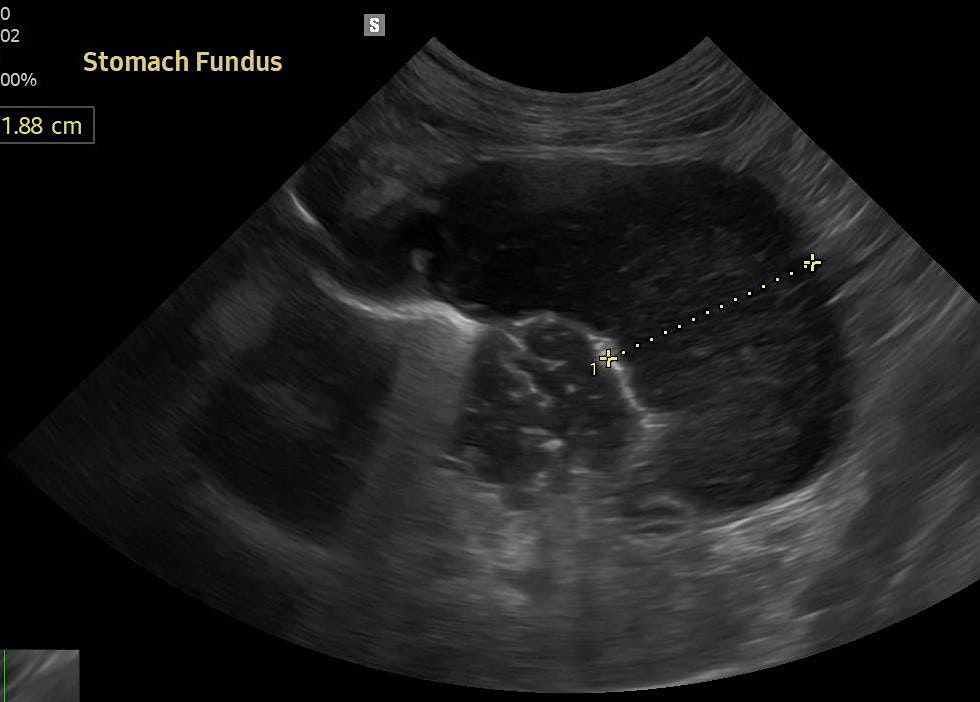

Ready to take the guesswork out of diagnostics? Join us for a dynamic and hands-on ultrasound class designed to boost your skills and comfort with this essential tool. Whether you’re a beginner or looking to sharpen your technique, this class will walk you through core concepts, probe positioning, and image interpretation for both abdominal and basic thoracic scans.

You’ll get guided practice and gain real-time feedback to help turn those gray-scale images into clear clinical answers. Learn how to spot what matters—and when to act on it.